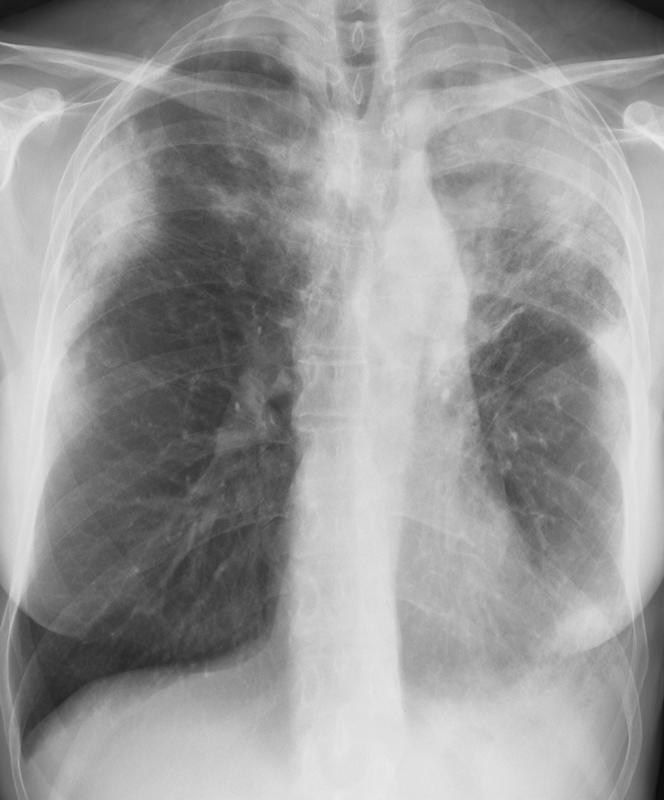

eosinophilic pneumonia